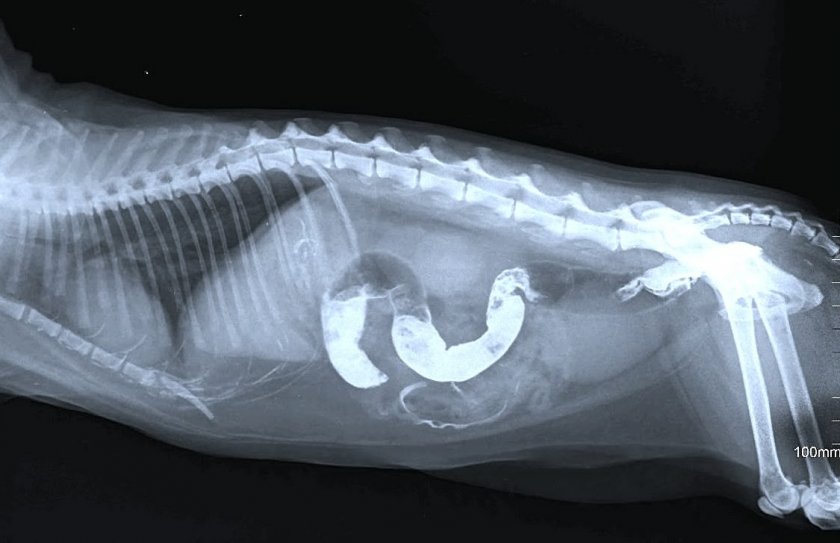

При попадании инородного предмета в желудок тоже имеет значение, какой именно предмет съела собака. Часто это невозможно определить, и приходится разбираться только с последствиями. Важно избежать двух вещей: кишечной непроходимости и повреждения внутренних органов острыми краями (в таком случае обычно наступает уже понос с кровью).

Небольшие предметы гладкой формы (например, бусинки) выйдут из организма собаки самостоятельно. Но более крупные предметы могут перекрыть выход каловым массам и попросту застрять внутри. Если у щенка диарея сменяется затруднением дефекации или ее полным отсутствием – нужно обратиться к врачу. В ветклинике извлекут посторонний предмет из ЖКТ.

Диагностировать болезнь ветеринар может после проведения анализов, изучения УЗИ и рентгеновского снимка ЖКТ